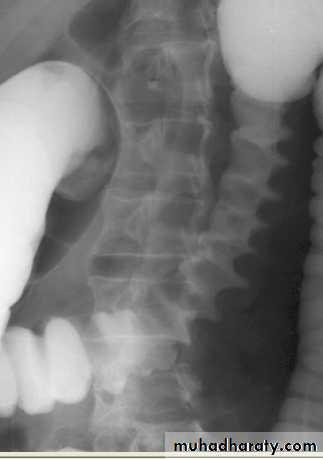

3. Vascular calcification: e.g. aortic aneurysm which best assessed on lateral film